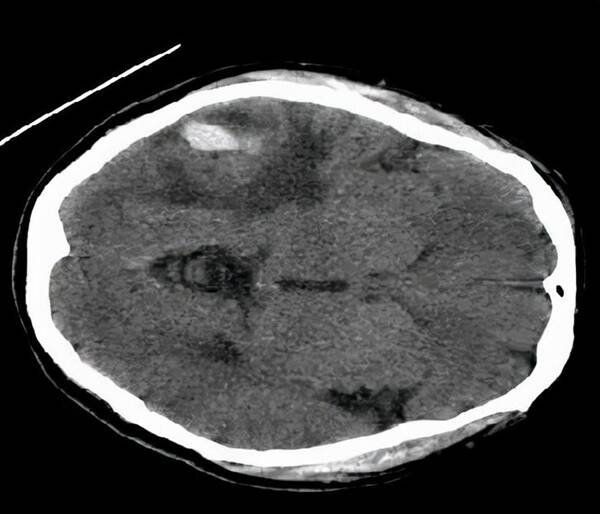

53歲的張先生以“突發(fā)意識不清4小時”代訴入院。入院時患者淺昏迷,極度煩躁。頭顱CTMRI提示:右顳葉占位病變伴出血,病灶呈不均勻強化,中心囊變,考慮高級別膠質(zhì)瘤。

術后CT